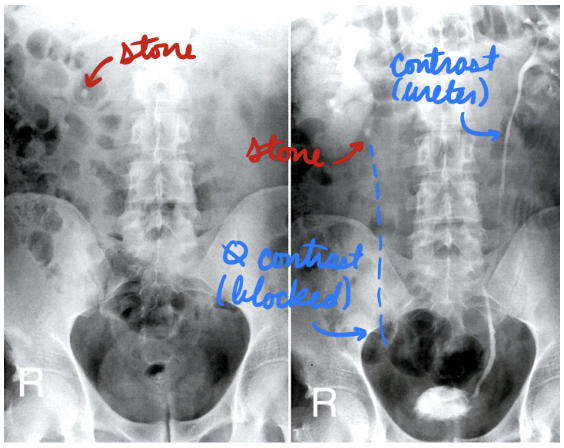

Nephrolithiasis: X-Ray

Intravenous pylogram (IVP)

X-ray + contrast

Rare → Use CT instead